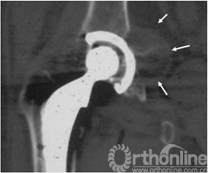

7例术前发现假体周围炎性假瘤患者,均进行聚乙烯磨损和线性磨损率测量。聚乙烯磨损表现在骨盆正位X线片上为聚乙烯内衬不对称(图2),两侧差值为股骨头偏移距离。本组病例股骨头偏移距离为2.00mm~7.12mm,平均3.57mm。

图2  X线片上AB=A’B’,表示聚乙烯无磨损,如果AB≠A’B’,则表示内外侧股骨头不对称,存在聚乙烯磨损